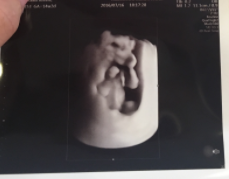

14週0日(14w0d・女の子)|ひろみんみん さん(28歳)

エコー写真撮影時のエピソード:

エコー写真を先生から渡された瞬間に、ピースをしている(ように見える)我が子に気づいてびっくりしました。

見れば見るほどピースに見えて、家族や友達にも見せています。愛嬌のある子が生まれてくるのだろうと楽しみにしています。